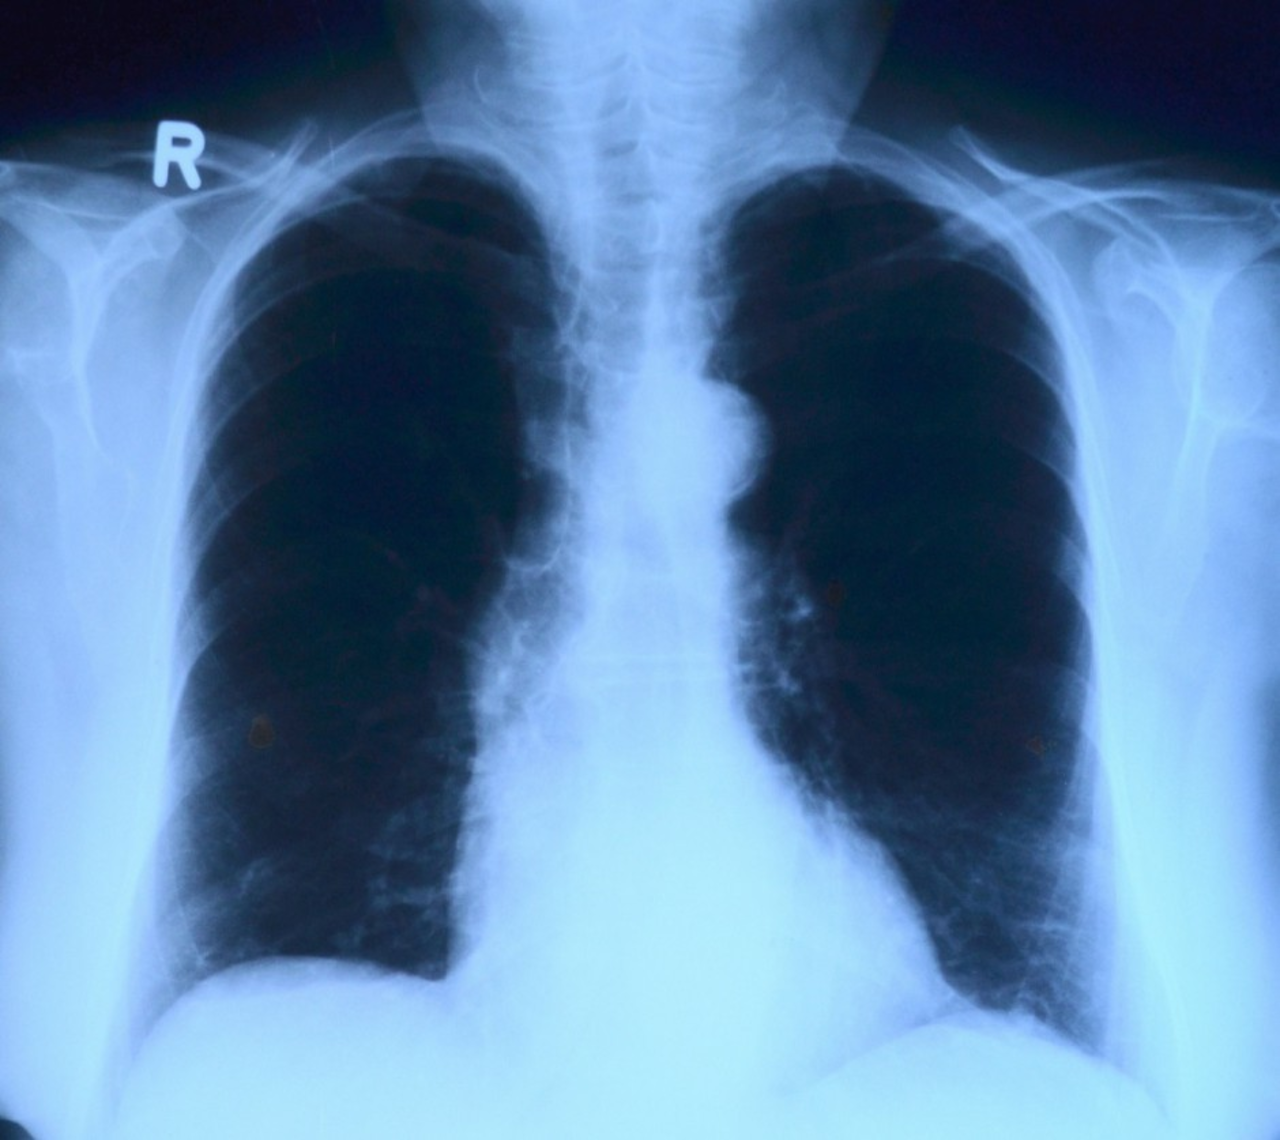

Dla wielu pacjentów zakażenie koronawirusem Sars-Cov-2 nie kończy się ustąpieniem najbardziej charakterystycznych objawów bądź zakończeniem kwarantanny. Coraz więcej pacjentów ma powikłania pocovidowe dotyczące układu oddechowego oraz szereg innych dolegliwości.

Większość osób przechodzi zakażenie koronawirusem łagodnie lub nawet bezobjawowo. Jednak nawet kilka miesięcy po przebytej infekcji niektórzy mogą zmagać się z szeregiem powikłań, wśród nich jest m.in. uszkodzenie miąższu płuc, schorzenia nerek, wątroby, zmiany skórne czy powikłania w obrębie układu sercowo-naczyniowego.

– Obecnie w swojej praktyce spotykam coraz więcej pacjentów, którzy przebyli chorobę Covid-19 i mają powikłania ogólnoustrojowe, jednak głównie ze strony układu oddechowego. Często te zmiany widać na wykonanym zdjęciu radiologicznym klatki piersiowej czy w tomografii komputerowej, ale też sami pacjenci skarżą się na duszności, ogólne osłabienie, zmniejszoną saturację krwi, temu wszystkiemu towarzyszą również  objawy kardiologiczne – mówi dr Zbigniew Bajor, pulmonolog.